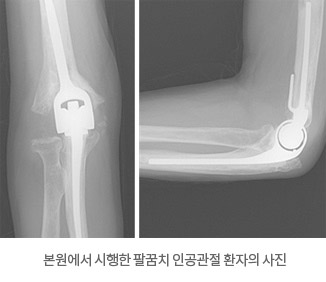

- └ 팔꿈치 관절염

- └ 팔꿈치 강직

팔꿈치 강직

팔꿈치 관절 불안정증